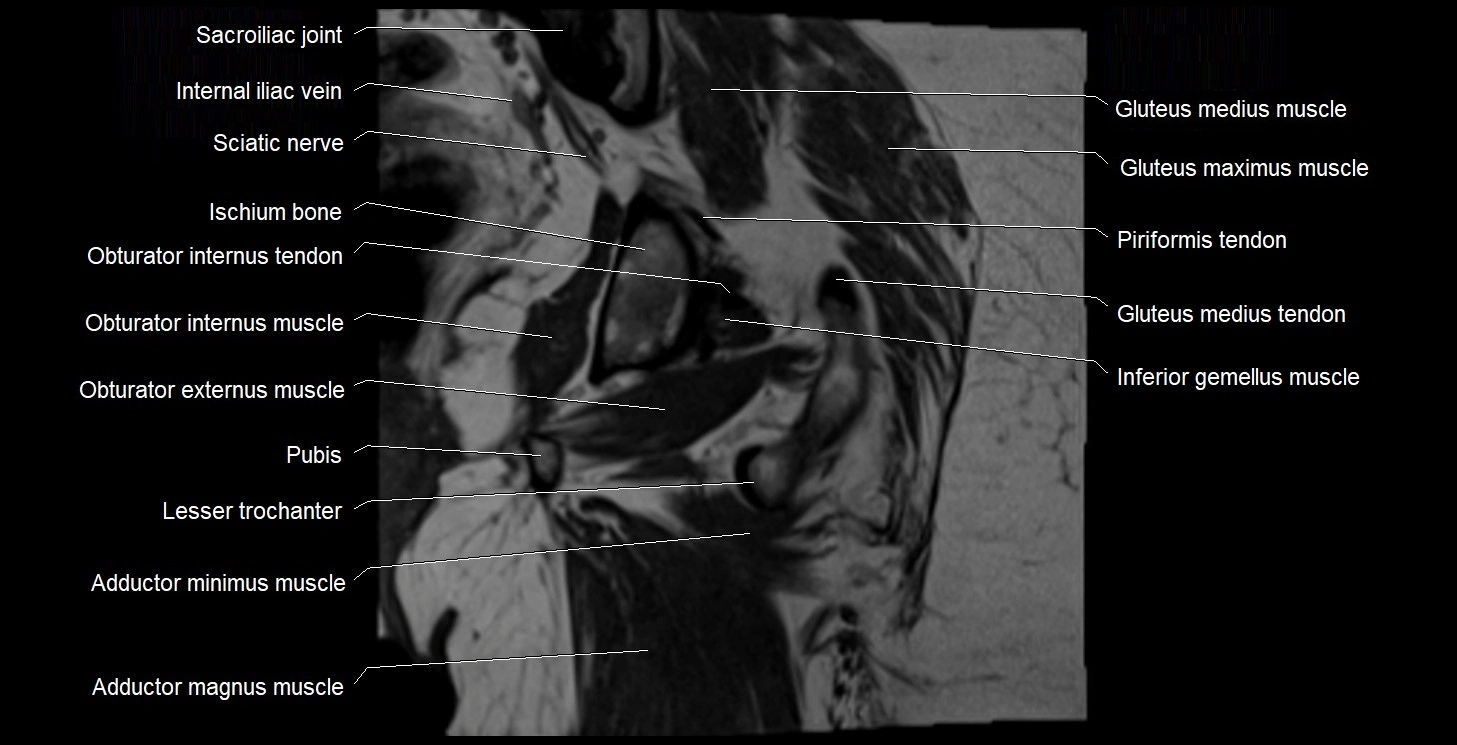

- Adductor magnus muscle

- Adductor minimus muscle

- Gluteus maximus muscle

- Gluteus medius muscle

- Gluteus medius tendon

- Inferior gemellus muscle

- Lesser trochanter

- Obturator externus muscle

- Obturator internus muscle

- Obturator internus tendon

- Sacroiliac joint